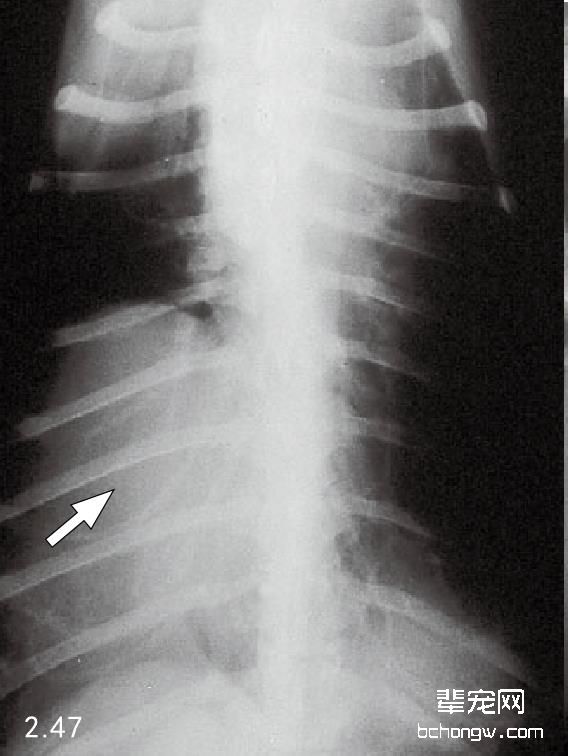

X线检查 侧面影像中,前部胸腔纵隔肿块引起气管偏离,心脏后侧移位和前侧心脏边缘消失;在背腹侧影 像中前部纵隔增宽和肺前叶后侧移位(图2.44和图2.45)。胸腔壁肿瘤通常引起软组织膨胀,导致邻近的肋骨移 位,作为额外的胸膜肿块延伸进入胸腔(图2.46和图2.47)。

图2.47 与图2.46同只犬的背腹侧胸腔X线片(箭头所示)。